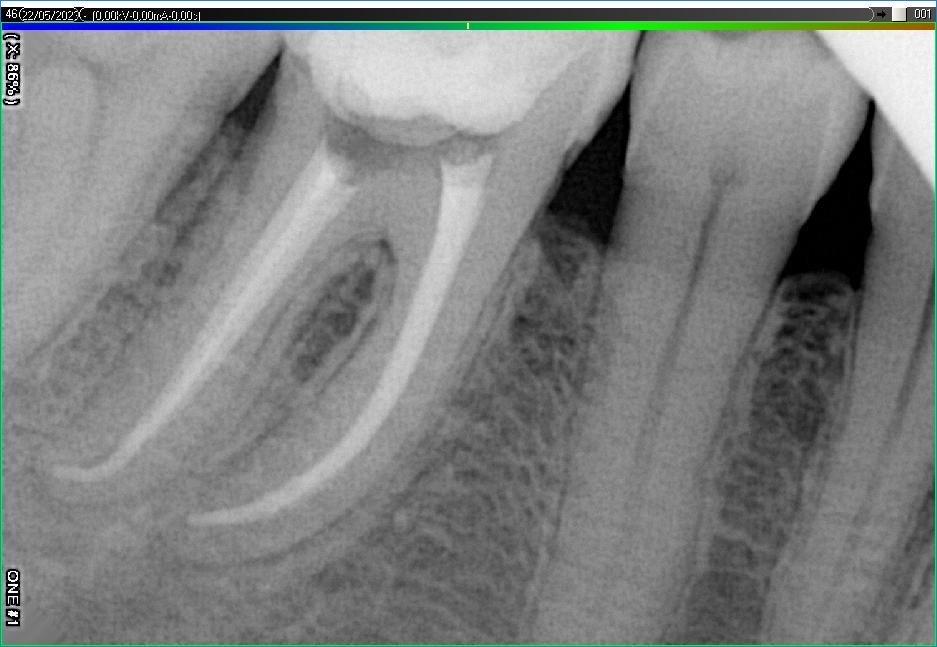

Вилучення інструменту з каналів зуба